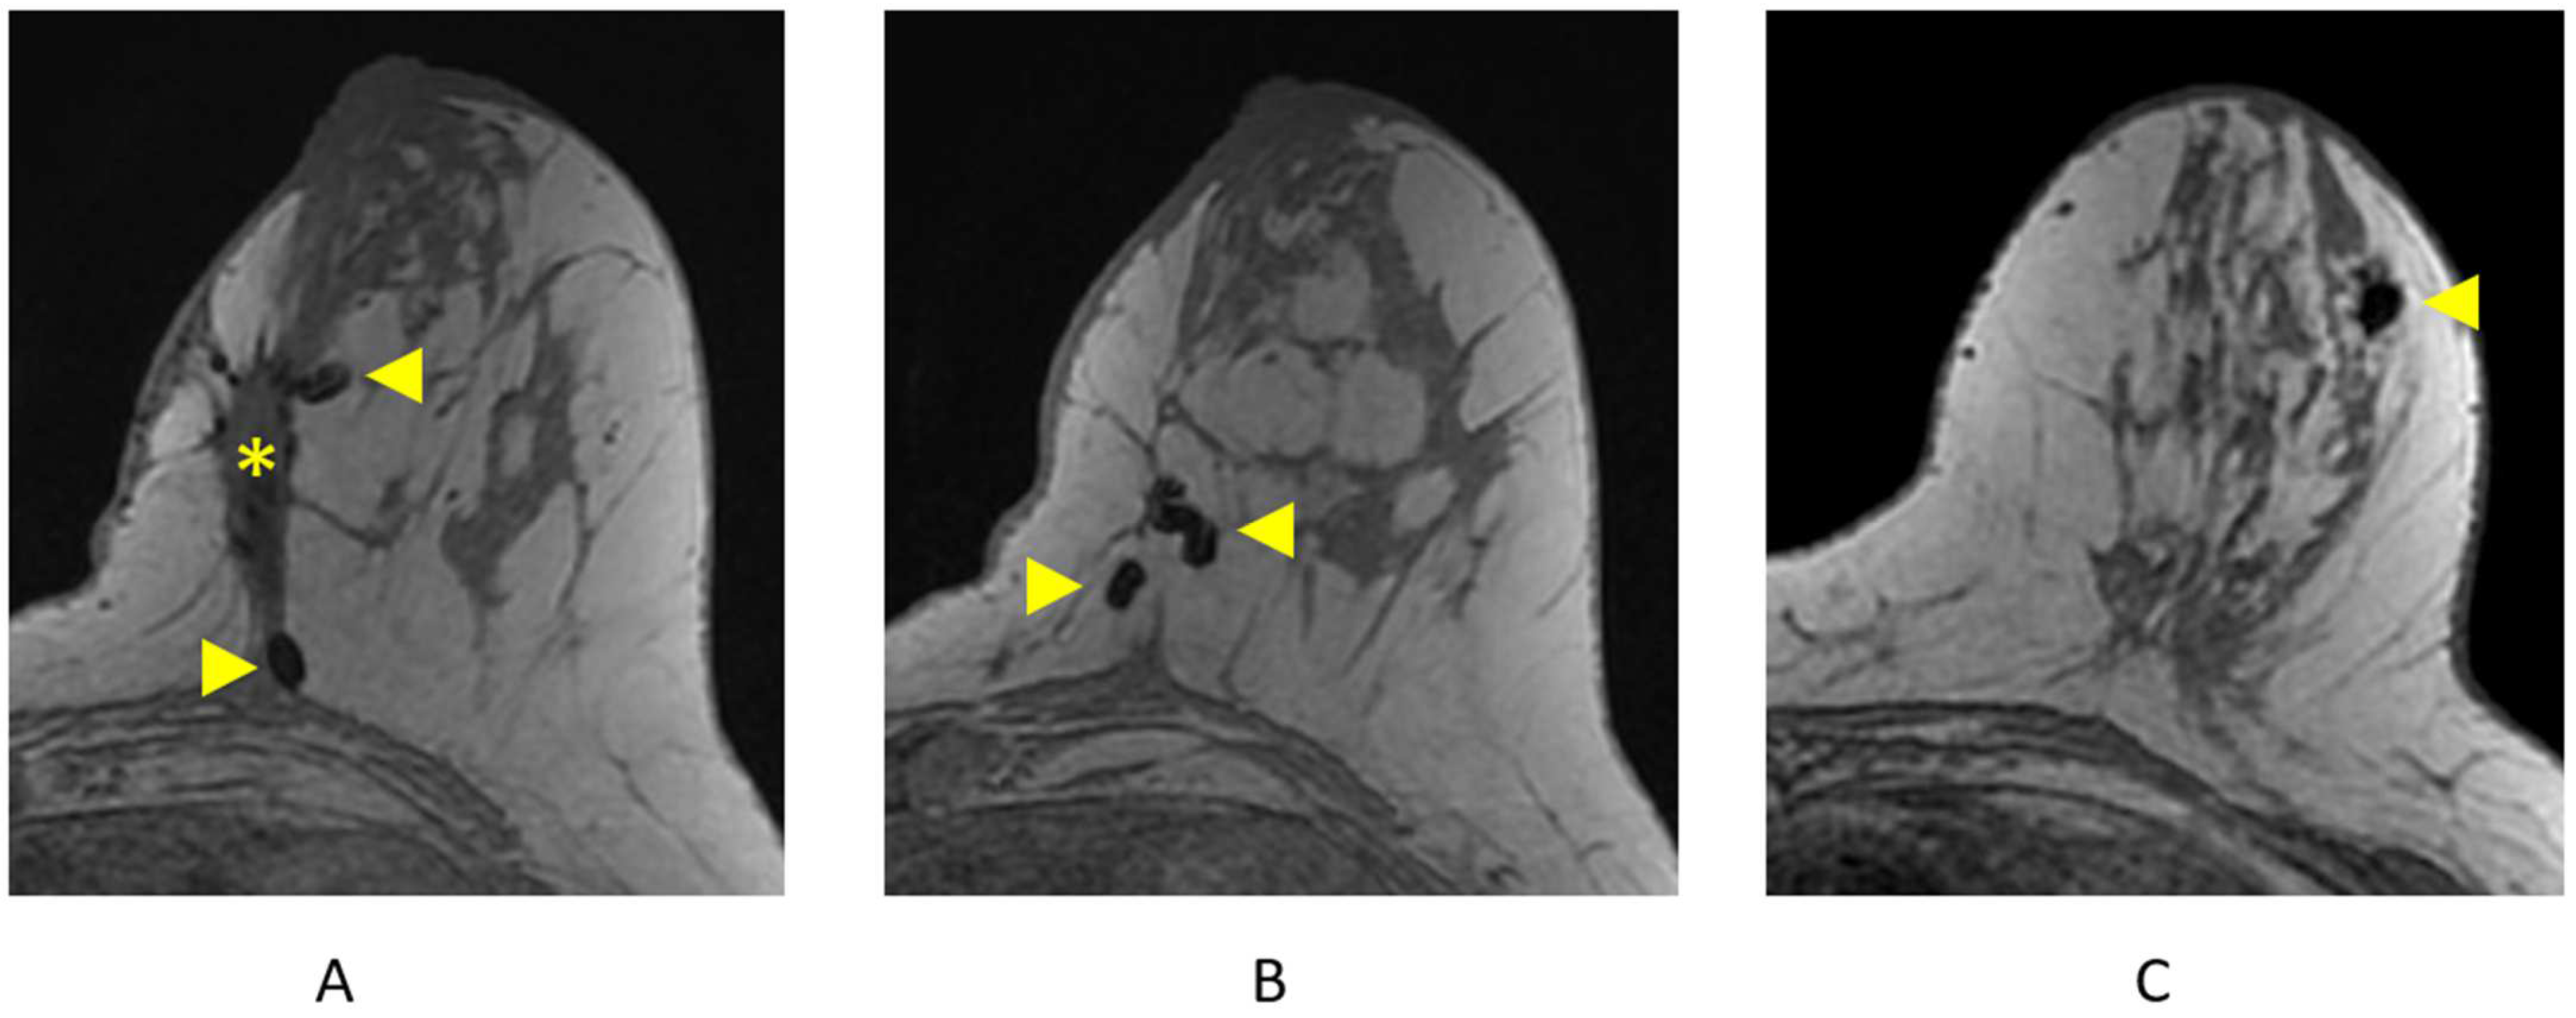

4.1.2. Identifying Surgical/Biopsy Clips

Clips are best visualized on the pre-contrast T1-weighted non-fat-suppressed sequence and are represented as areas of focal susceptibility artifact (“signal void”) (Figure 12). Careful correlation with recent mammography is important to confirm the presence of surgical or biopsy clips, as focal areas of susceptibility artifact may also represent other processes, including hemosiderin deposition.

Figure 12.

Surgical and biopsy clips on axial T1-weighted breast MRI. (A) Lumpectomy site (asterisk) and areas of focal susceptibility representing surgical clips (arrowheads); (B) additional surgical clips (arrowheads); (C) focal susceptibility artifact representing a breast biopsy clip/tissue marker (arrowhead).